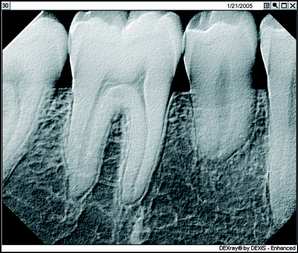

Bottom: Image Enchancement using the Relief Mode

First, there's the critical matter of diagnostic capability. I don't care what other dentists might say who are still trying to convince themselves they should stick with film technology, you can improve your diagnostic capability significantly using digital radiography. With digital, you're looking at an image that fills a 19-inch computer screen and not a film image the size of a postage stamp. Using the software-based digital radiography's image enhancement functions such as magnification, brightness control, and heightened contrast, you can bring out aspects of the X-ray that simply aren't visible on film, including such things as tiny fractures and imperfections that you might very well miss on film. Once you begin to practice using magnification for vision, you wouldn’t practice without it. It’s the same with the digital x-rays.